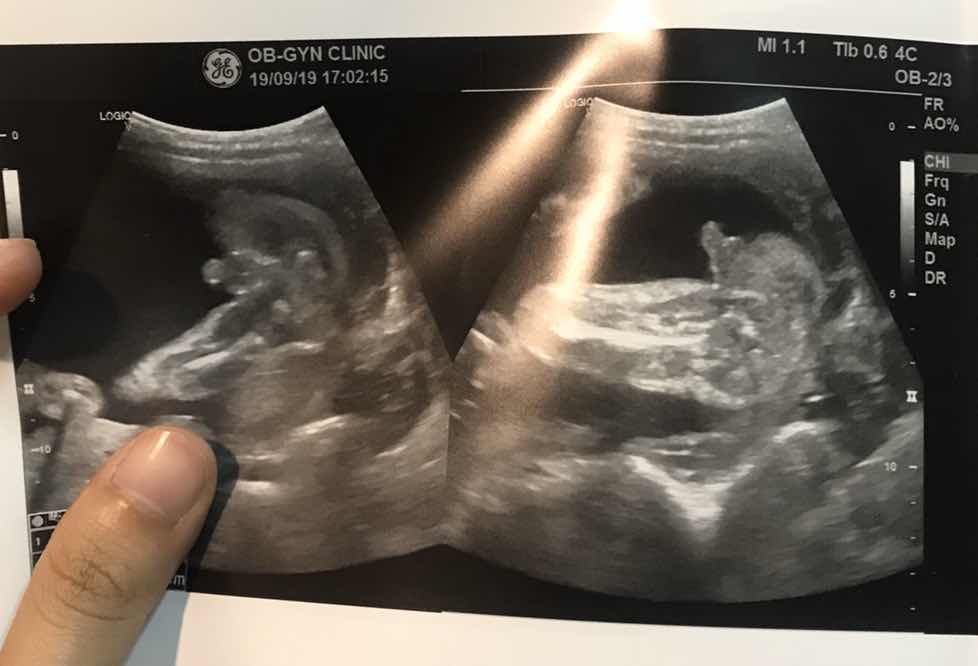

ลูกสาวจ้า ชัดมาก

น้องผู้หญิงสินะคะ >

เหมือนกันเลยค่ะ